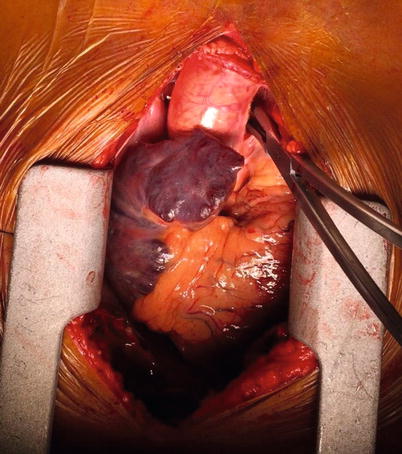

Fig. 37.3

CT angiogram (with reconstruction) demonstrating a penetrating injury to the innominate artery